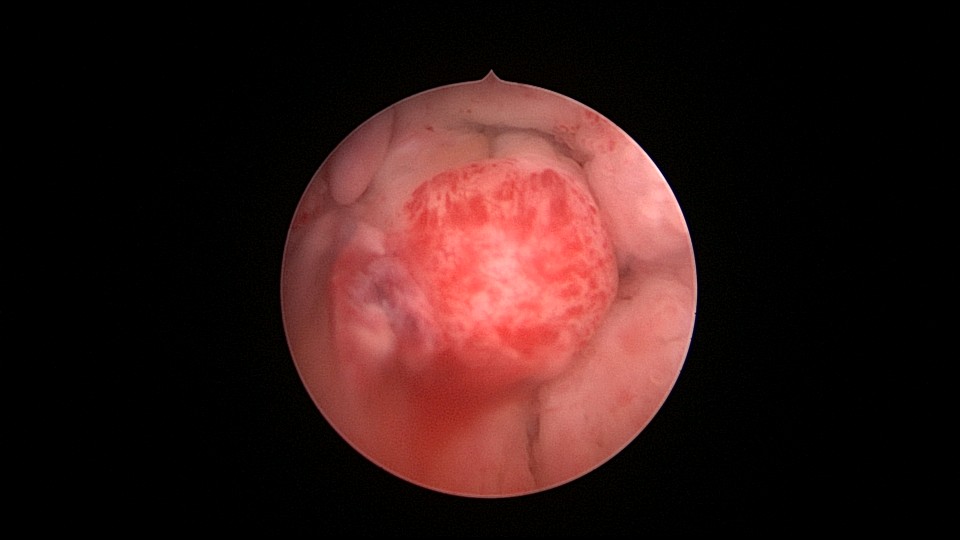

患者55岁,G1P1,顺产1次。安环31年,绝经3年,妇科检查发现宫颈外口息肉,B超宫腔未见分离暗区。子宫前位,宫腔镜见宫颈管下段多发息肉,宫颈内口粘连,宫腔少许淡黄色脓液流出,宫型环位置正常,被镜鞘推挤变形。助手单极电针切除宫颈管息肉时进针过深,引起较多出血,视野不清楚,接手手术,先止血、切除息肉,然后异物钳取出节育环,宫腔无其他异常。病检为宫颈管息肉。